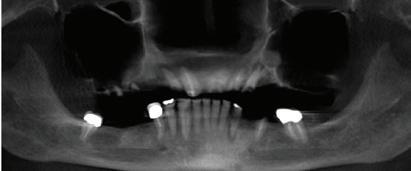

New Solutions For Dentures and Dental Implants

Dentures are a good replacement option for patients who are missing all of their teeth, but only if they fit well.

Impact on the bone by continuous hitting and pressure of a denture against the jaw every time you eat can make the bone underneath the denture go away. This causes the denture to become loose and slip. It may create the need for using paste or other means to hold the denture in place. Slipping dentures can make eating certain foods very difficult for patients. This happens most often with lower dentures.

How Can Dentures Fit Well For a Long Time?

Dental implants can be placed under the denture. Implants have offered the possibility of fully replacing teeth for over 30 years and are very safe and effective. When you make the denture stable by “snapping” it onto dental implants, you can provide a better level of comfort for the denture-wearer, and create new strength for eating the foods patients love.

Dental implants are very much like your natural teeth. They are quite easy to get used to, and they can reduce the amount of stress to the bone and jaw by helping provide an anchor for support. The implant acts as a natural root to help prevent additional bone deterioration and helps to deliver long lasting function.

Does Every Denture-Wearer Qualify?

This depends on the amount of bone loss that has already taken place. If the denture has been in place for many years and the ridge of bone under it is very thin, you may need to have a special scan done to decide if you are a candidate for the procedure. This scan will also look for any other defects that may be present to make sure you are healthy. Since implants are meant to last for a very long time, your health and wellness are important to the outcome.